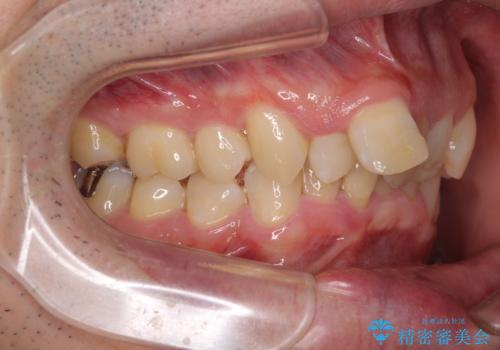

- ぶつけて前歯が折れてしまったとのことで来院された患者様です。

折れてしまった前歯は軽傷であり、歯内の歯髄に影響は及んでいませんでした。

通常では速やかにオールセラミッククラウンにて補綴治療を行うのですが、デコボコしている歯列も気になっていたため、事前に矯正治療を行うこととしました。

上顎歯列の叢生が著しかったため、上顎左右第一小臼歯2本を抜歯し、目立たないワイヤー装置にて治療を進めることとしました。